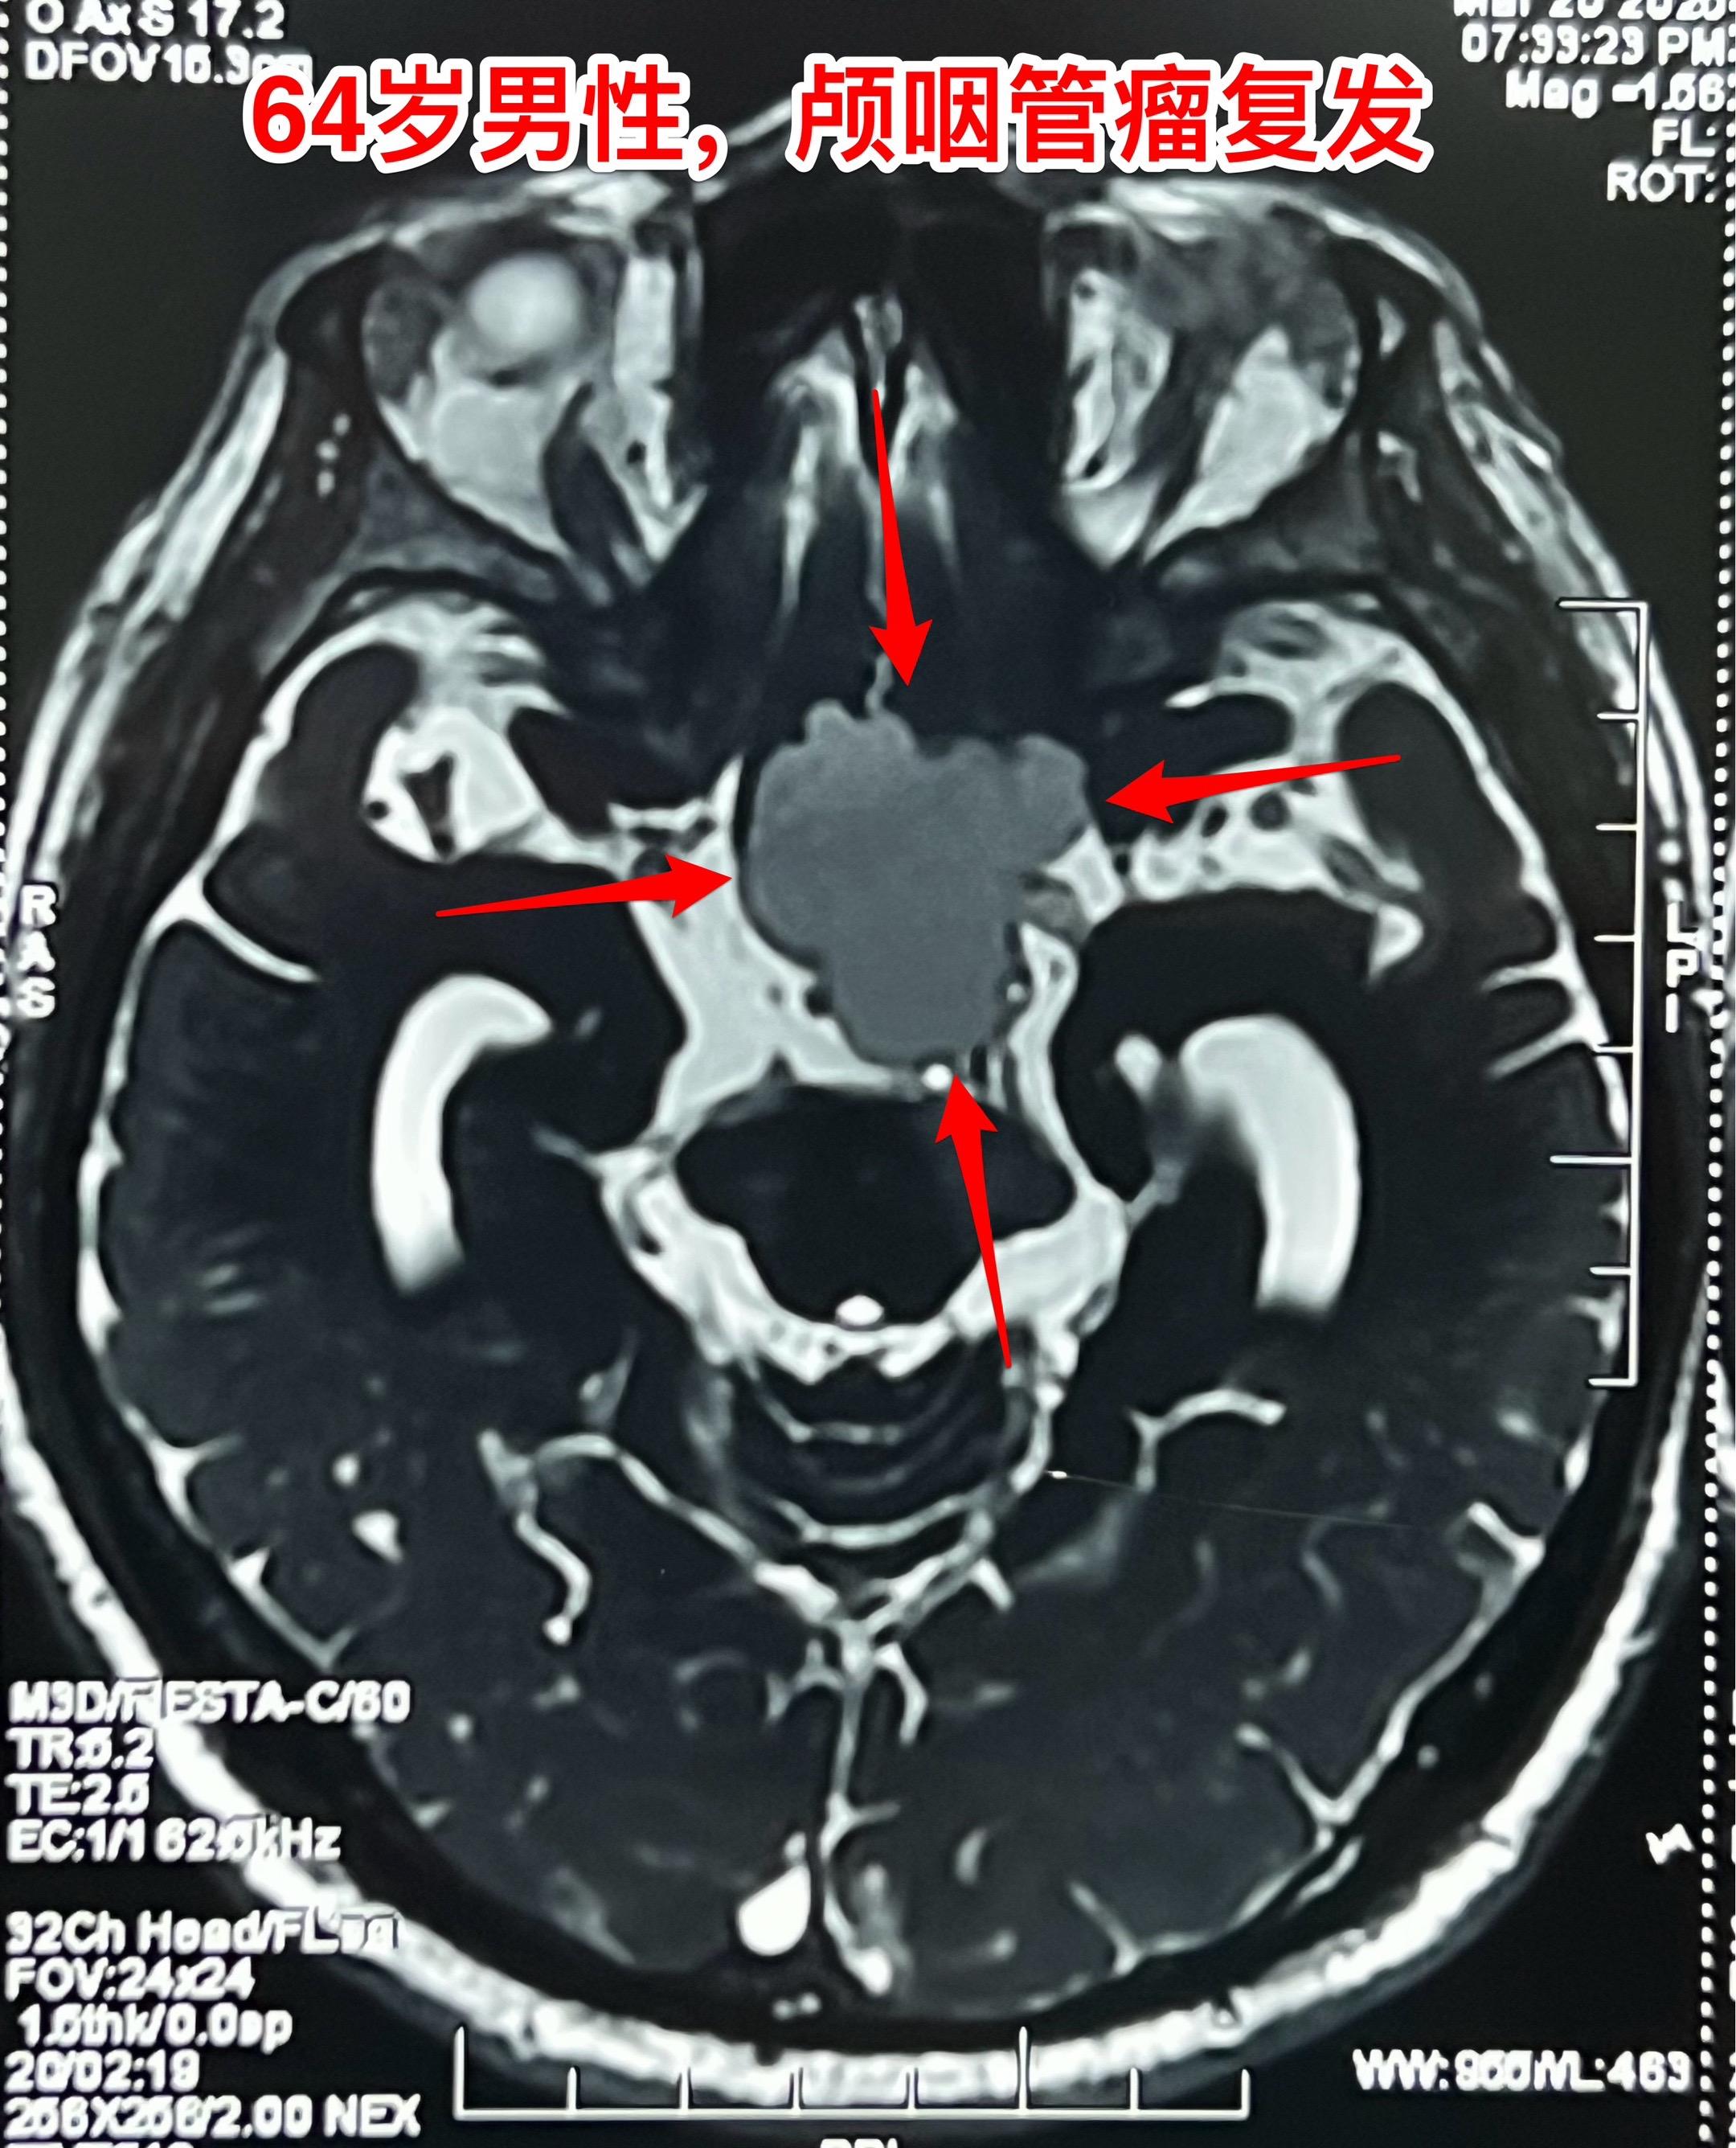

3月28日两个颅咽管瘤手术 两个都是经鼻手术手术后复发的颅咽管瘤手术。我采用了开颅手术。 第一个是64岁山西人,颅咽管瘤手术后再次出现视力下降,复查磁共振显示肿瘤复发。肿瘤是囊性乳头型颅咽管瘤,没有钙化。 第二个是32岁的湖南小伙。肿瘤有钙化。 今年春节后我科颅咽管瘤中经鼻手术后复发的病人比例明显升高了。与近十年经鼻内镜手术广泛开展是有关系。 无论是哪种手术方案,只有效果好、复发率低,病人才会满意。